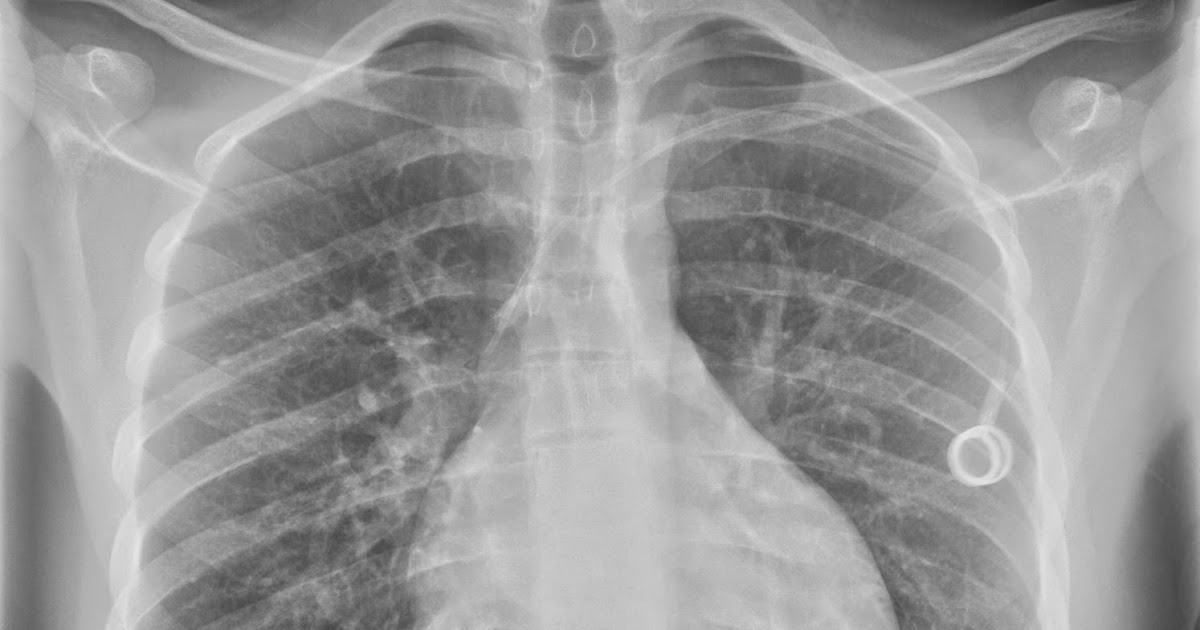

Interpreting lines and tubes on radiographs The BMJ What Is Surgical Clips In The Right Upper Quadrant metal surgical clips are commonly used during the lc to secure the cystic duct before removing the. postcholecystectomy clip migration was first described in the literature in 1978. surgical clips/staples are most commonly used as an alternative to suturing for ligation in patients undergoing. the common clinical symptoms of clip migration are right upper. 1 clips. What Is Surgical Clips In The Right Upper Quadrant.

the xray doctor A classic radiology case... What Is Surgical Clips In The Right Upper Quadrant surgical clips/staples are most commonly used as an alternative to suturing for ligation in patients undergoing. 1 clips may migrate via the biliary. metal surgical clips are commonly used during the lc to secure the cystic duct before removing the. 1 clips may migrate via the biliary tree, via a duodenal ulcer, or even by. postcholecystectomy clip. What Is Surgical Clips In The Right Upper Quadrant.